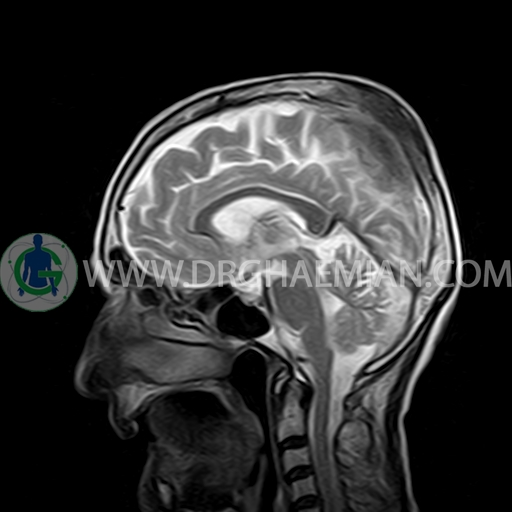

ام آر آی مغز با استفاده آهنربا های قوی و امواج رادیویی تصاویری از مغز و بافت های عصبی پیرامونی آن ایجاد می کند. در این کیس مننژیوم به همراه هیپراستوز استخوانی سمت چپ دیده می شود.

BRAIN MRI

(Without contrast)

Technique:Axial FLAIR, Axial, sagittal, FSE T2, coronal T1 .

The interhemispheric fissure is centered on the midline .

No abnormalities are seen in the basal ganglia, int. capsule, corpus callosum, Thalamus and tectal plate.

The sella and pituitary – pineal g .are normal and parasellar, suprasellar structures are unremarkable.

The cerebello pontine angle area appears normal on each side.

The internal acoustic meatus has normal width .

Major intracranial vascular structures, pericavernous spaces and visualized intracranial nerve complex are normal.

The paranasal sinuses are clear and aerated with no evidence of bone erosion or destruction, fluid collection, cystic retention and mucosal thickening.

a well – defined dural based mass lesion ( 27x55mm ) in left parietal region with signal change in adajacent bone suggestive for meningioma with bone hyperosteosis

mass effect & edema in left parietal lobe

are seen

COMMENT : MRI with contrast is recommended .